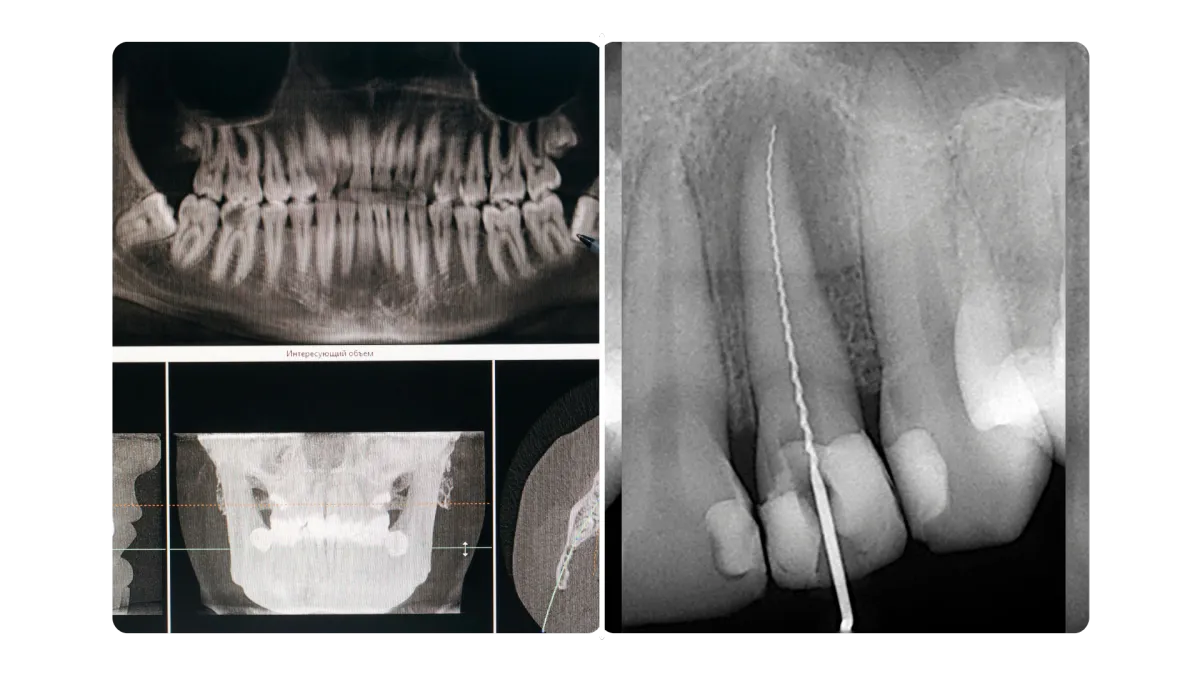

En algunos casos se requieren radiografías o estudios complementarios para planificar correctamente el procedimiento.